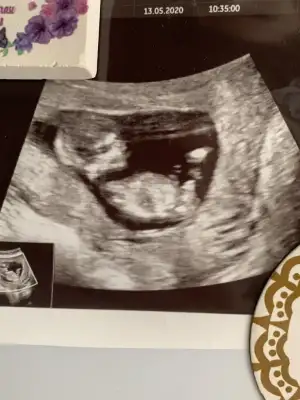

Iyi aksamlar hanımlar. bizede yorum yapabilir misiniz? kardesimin ultrasyon resmi. şimdiden tesekkur ederim

Eklentiler

• IMG-20200516-WA0004.webp

IMG-20200516-WA0004.webp

27,1 KB · Görüntüleme: 70